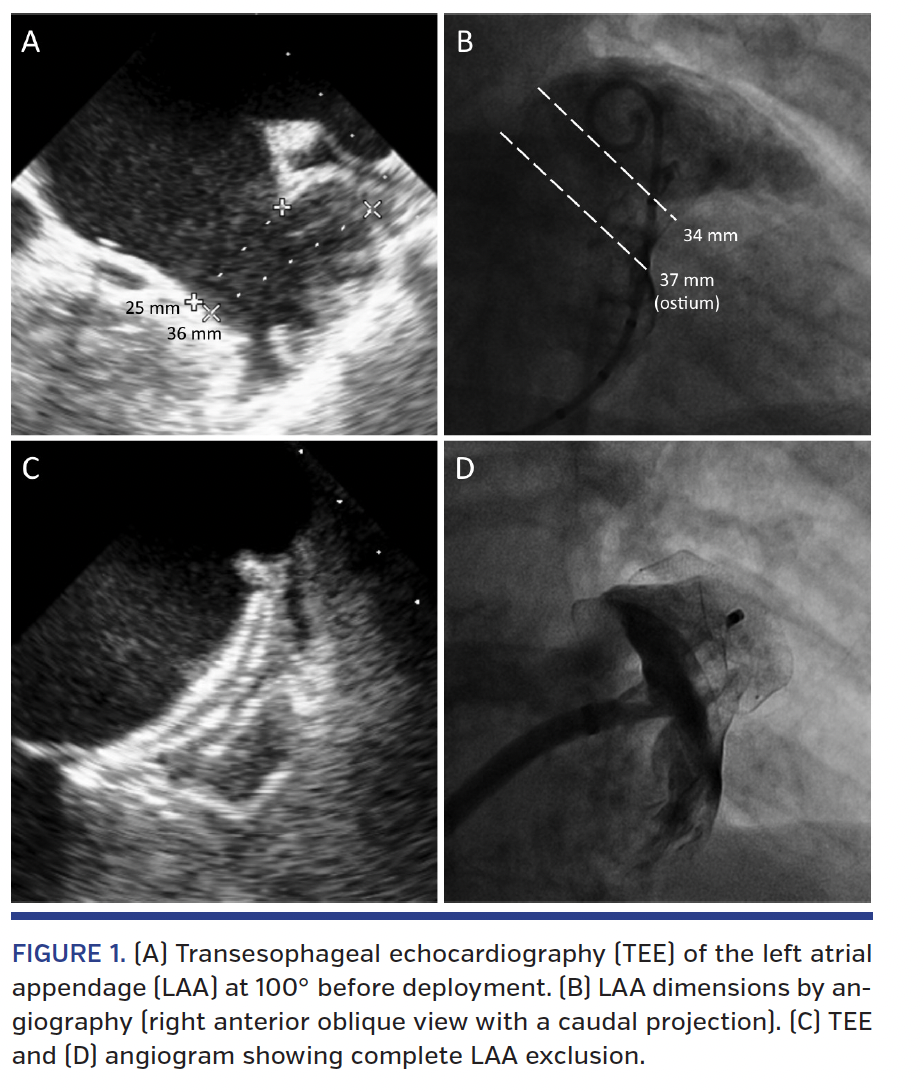

An 88-year-old man with permanent non-valvular atrial fibrillation and contraindication to anticoagulation was referred to our institution for percutaneous left atrial appendage (LAA) closure. A severely enlarged LAA was documented by preoperative transesophageal echocardiography (TEE), which demonstrated a landing zone ranging from 26 mm at 87° up to 36 mm at 100° with a neck of 25 mm (Figure 1A). LAA angiography from multiple projections confirmed a mean landing zone diameter of 34 mm (Figure 1B). Neither the Watchman device (Boston Scientific) nor the first-generation Amplatzer Cardiac Plug (St. Jude Medical) was compatible with such remarkable measures. Although the lobe of the LAA was roomy enough for any available device, the neck was within the appropriate range for attempting the implantation of the novel Amplatzer Amulet device (St. Jude Medical). A 34 mm Amulet was selected and successfully implanted (Figures 1C and 1D). The wide lobe – which has more and stiffer stabilizing wires and a longer waist compared with the Amplatzer Cardiac Plug – acted like an anchor at the level of the neck and efficiently stabilized the system. In fact, even without evidence of compression at fluoroscopy, the excellent anchoring was demonstrated by vigorous tugging (Video 1). The large disc, which is designed to prevent embolization from periostial trabeculae, provided full coverage of the very large LAA ostium (38 mm at 48° TEE and 37 mm at angiography). Control TEE confirmed the absence of peridevice leaks or mitral valve impingement, and follow-up was uneventful.